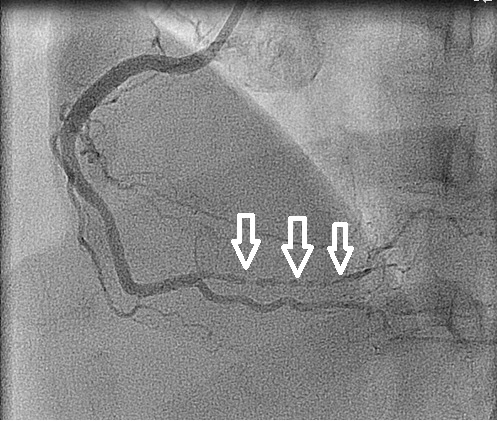

Figuur 3 – Rechterkransslagader (RCA) vóór toediening nitroglycerine intracoronair.

De witte pijlen geven het traject aan waar ernstige spasme aanwezig is.